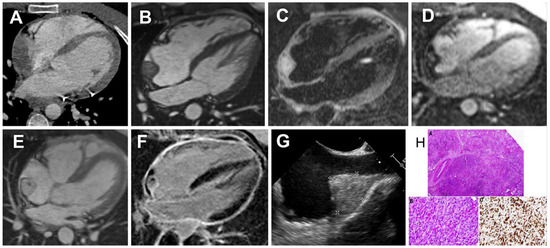

A previous healthy 26-year-old male was admitted by ambulance after he suffered a syncope during his work in a supermarket and an ambulance was called. In the past 6 days, he had complained of dyspnoea and chest pain, mostly during inspiration, and his general practitioner started inhalation therapy, which was unsuccessful. Before the syncope, he described no exacerbation of chest pain or dyspnoea. After arriving in the hospital the patient showed signs of bradycardia and had a second syncope during mobilisation. On telemetry asystole for 5 seconds was noticed and one dose of atropine 0.5 mg was given. Initial blood pressure was 95/60 mm Hg and after it dropped to 60/45 mm Hg in the first minutes, noradrenaline and adrenaline were administrated for a short time. Transthoracic echocardiography (TTE), performed in the emergency department, revealed cardiac tamponade. The ECG showed sinus tachycardia (after noradrenaline and adrenaline administration) with an S1Q3 pattern and diffuse ST-elevations in II, aVF, V2-V3, V5-V6, but no low voltage. Emergency pericardiocentesis was conducted. Cytological analysis of the pericardial fluid showed activated mesothelial cells but no malignant cells. By thoracic computed tomography (CT) an aortic dissection was ruled out, but a heterogeneous mass within the right atrium (RA) was seen in an otherwise unremarkable scan (Figure 1A). Cardiac magnetic resonance imaging (CMR) 2 days later revealed a 23 × 25 × 39 mm broad-based tumour, located at the roof of the RA and near the entrance of the superior vena cava (SVC), with inhomogeneous appearance and oedema in the native sequences, quick contrast enhancement during first-pass perfusion and inhomogeneous late gadolinium enhancement with central necrosis, very suspicious of a highly vascularised malignant tumor (Figure 1B–F). No other evidence of malignancy was found in a whole-body positron emission tomography (PET)-CT.

Intraoperatively, extended tumour excision up to the sinus node and SVC, pulmonary veins and inferior vena cava, as well as pericardectomy and excision and reconstruction of the phrenic nerve were performed. The right atrial wall was completely reconstructed by a pericardial patch. Histopathology identified a high grade angiosarcoma of the RA with clear margins of resection (Figure 1H). After 18 days of hospitalisation, the patient was discharged in a good condition for rehabilitation. Planed follow-up CT 4 weeks after the resection and before the start of chemotherapy showed no signs of local complications or relapse. The oncology board decided on four cycles of adjuvant chemotherapy with epirubicin and ifosfamidecycles.

In our patient, CMR was critical for further differentiation of the findings. The RA tumour was broad-based, inhomogeneous, with quick contrast uptake in the first-pass perfusion and and inhomogeneous late gadolinium enhancement with central cores of contrast deficiency suggestive of cystic or necrotic areas. Based on tumour localisation, morphology (inhomogeneous tumour with necrotic/cystic areas), infiltration with haemorrhagic pericardial effusion and perfusion (very well vascularised), a malignant tumour was strongly suspected (angio-, rhabdo-, leioor undifferentiated sarcoma). Ultimately, histopathology established the diagnosis of an angiosarcoma. Unfortunately, only limited data on optimal treatment and prognosis of cardiac angiosarcomas are available. Complete resection should be the mainstay of treatment. Patients who undergo surgery have a better outcome than those without surgery. Surgery may also be considered to relieve symptoms [6]. But even with complete surgical resection, the 5-year survival rate is low. The impact of adjuvant, anthracycline-containing chemotherapy in soft tissue sarcoma in general and in its subtypes is not clear.

Figure 1. Multimodality imaging and histologic images of the right atrial angiosarcomaat first presentation. (A) CT scan demonstrating a right atrial mass, (BF) cardiac magnetic resonance imaging (CMR): (B) SSFP still frame, (C) TIRM, T2-weighted image, (D) first pass perfusion indicating a highly vascularized tumor, (E) post-contrast SSFP still frame showing high uptake of contrast medium but also central hypointenseareas without contrast uptake, (F) late enhancement sequences demonstrate inhomogeneous late gadolinium enhancement with a central area without contrast medium uptake, suggestive for cystic or necrotic areas and very small residual pericardial effusion, (G) transesophageal still frame of the right atrial mass located at the entrance of the superior vena cava, (H) histological images of the angiosarcomawith upper and lower left picture showing atypical proliferation of endothelial cells with presence of abortive erythrocyte-filled vascular lumina, the lower right picture confirms the vascular nature of the neoplastic cells.